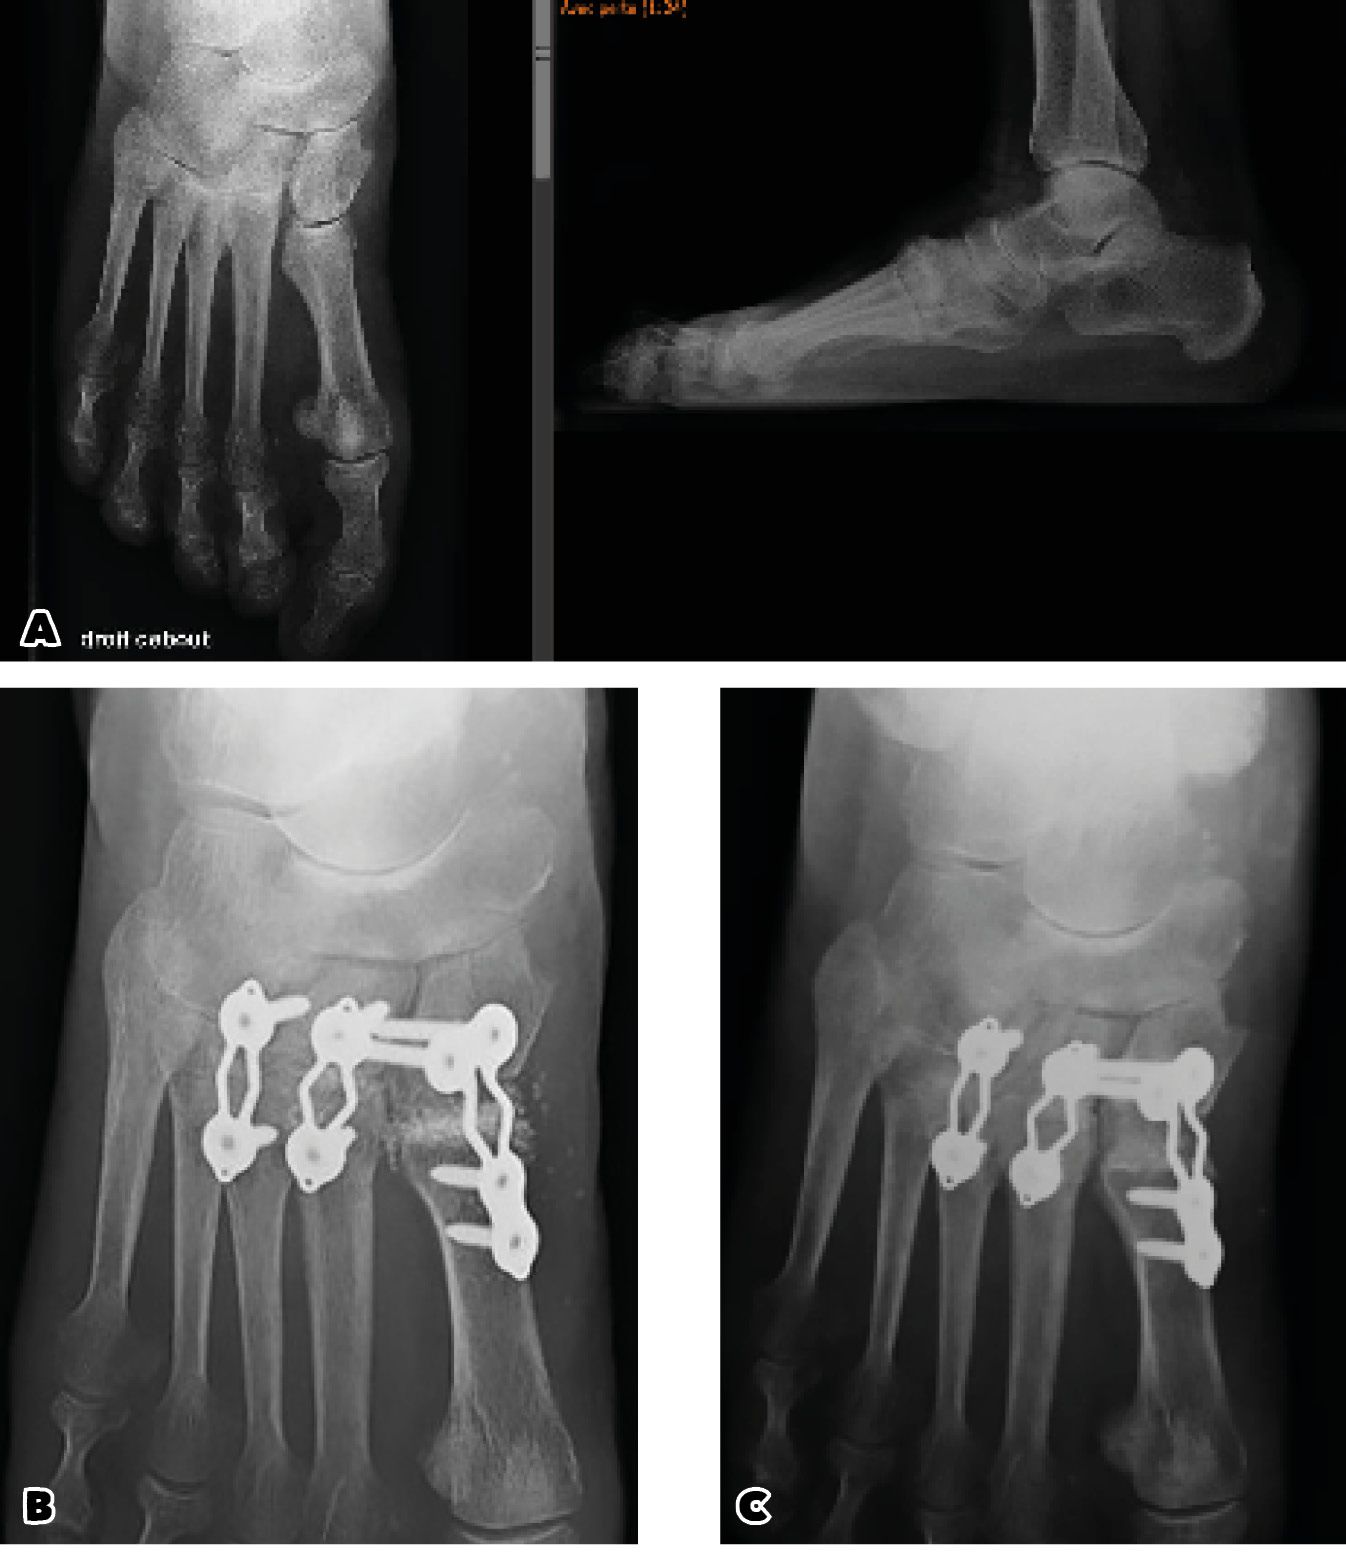

In fact, a distinction must be made between pure ligament injuries and osteoarticular injuries. Thus, immediate arthrodesis would give better results in cases of pure ligament damage because of the low healing capacity of the ligament structures. The question between osteosynthesis and immediate arthrodesis is not entirely clear but in the case of osteoarticular damage arthrodesis does make more sense (41). (Case 2)

Case 2: Mrs M. 66 years old painful osteoarthritis of the medial Lisfranc following an old trauma diagnosed as "sprain".

Preoperative radiographs: osteoarthritis of the medial Lisfranc

Bone fusion Immediate postoperative radiographs and at 1 year FU